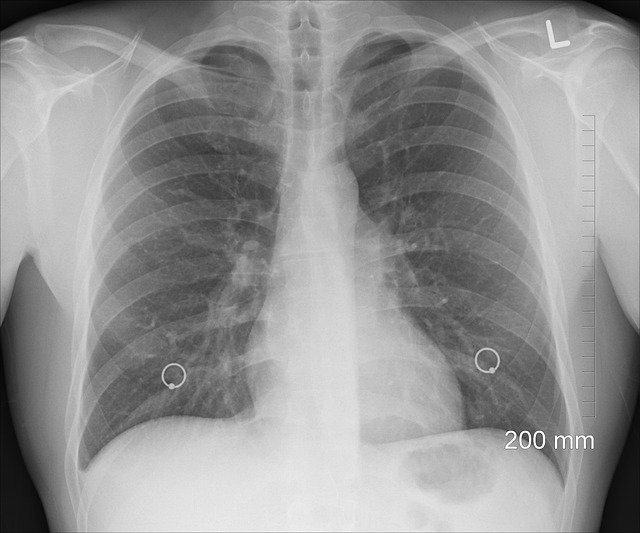

진단 방법:

1. **청진:** 한쪽에서 숨소리가 감소 또는 소실됨

2. **흉부 X-ray:** 기흉 진단의 기본 검사. 공기로 찬 흉막강 확인

3. **CT 촬영:** 작은 기포, 재발성 기흉 원인 파악에 유용

4. **산소포화도 측정:** 산소 교환 기능 확인

5. **혈액 가스 검사:** 산소, 이산화탄소 농도 측정

조기에 정확한 진단이 이루어질수록 합병증을 줄이고 회복 속도를 높일 수 있으므로, 기흉 의심 시 지체하지 말고 병원을 방문해야 합니다.